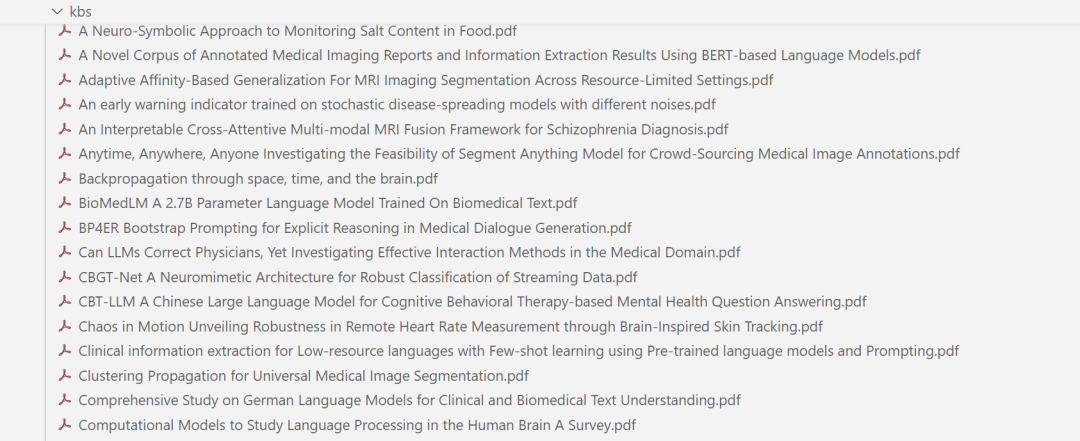

数据准备

以 ArXivQA 数据集为例,从 Papers-2024.md 中的100篇论文构建知识库和数据库,在准备数据之前需要先下载论文信息文件(内含论文链接),可以离线下载或者以下命令进行下载:

我们需要从两方面去准备数据(以医学领域为例):

📚 医学知识库:存储论文全文到指定目录,用于文献类问答。

📊 医学数据库:提取论文元信息(如标题、作者等)到本地数据库,用于统计类问答,论文信息如title、author等。

下面是获取到的PDF: